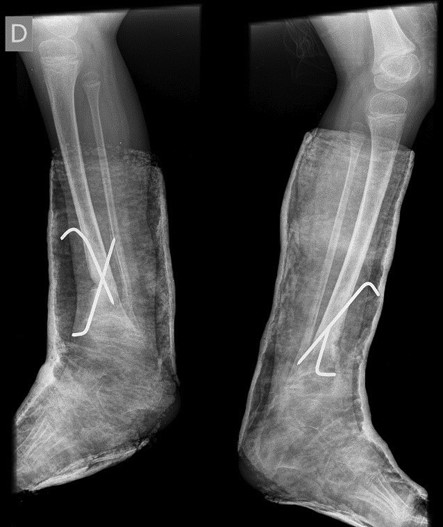

Surgical correction was scheduled. It was performed an opening wedge tibia osteotomy and filled the remaining gap with structural fibular graft. It was fixed with two crossed K-wires and cast immobilization. Both surgeries were performed at the same operative time (Figs 3 and 4).

The surgery was uneventful, after 6 weeks there was possible to observe healing of the osteotomy site so the cast and K-wires were removed.